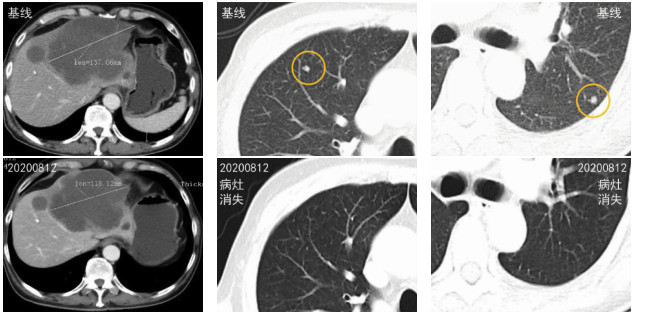

Clinical effect of programmed cell death-1 inhibitor combined with lenvatinib in treatment of advanced primary liver cancer and related adverse events

Ying TENG, Xiaoyan DING, Wendong LI, Jinglong CHEN

2021, 37(3): 606-610. DOI: 10.3969/j.issn.1001-5256.2021.03.020

Abstract(1621) HTML (589) PDF (1942KB)(93)

Abstract:

Objective  To investigate the clinical effect of domestic programmed cell death-1 (PD-1) inhibitor combined with lenvatinib in the treatment of advanced primary liver cancer and related adverse events.  Methods  A retrospective analysis was performed for the clinical data of 24 patients with advanced primary liver cancer who were treated with domestic PD-1 inhibitor combined with lenvatinib in Beijing Ditan Hospital, Capital Medical University, from January 1, 2019 to April 2, 2020, with 15 patients in the Camrelizumab+lenvatinib group, 7 patients in the Sintilimab+lenvatinib group, and 2 patients in the Toripalimab+lenvatinib group. During follow-up, Modified Response Evaluation Criteria in Solid Tumors was used to evaluate the treatment outcome of intrahepatic lesions, and RECIST1.1 was used to evaluate extrahepatic metastatic lesions. The Kaplan-Meier method was used to evaluate survival time.  Results  Among the 24 treatment-experienced patients, 11 achieved partial response, 7 achieved a stable disease, and 6 had disease progression, resulting in an objective response rate of 45.8% and a disease control rate of 75.0%. The median time to disease progression was 8.4 (95% confidence interval: 6.89-9.91) months. The incidence rate of adverse events was 54.17%, and the most common adverse events were fatigue (29.17%) and hypertension (25.00%).  Conclusion  PD-1 inhibitor combined with lenvatinib has a marked clinical effect in the treatment of advanced primary liver cancer, with a low incidence rate of serious adverse events, and thus it is a safe and effective treatment regimen.